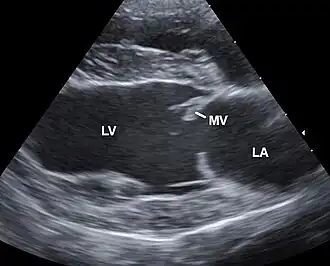

Auskultatorisch lassen sich häufig krankhafte Herzgeräusche infolge des mangelnden Schlusses betroffener Klappen nachweisen. Eine sichere Diagnose kann mittels Sonografie gestellt werden.